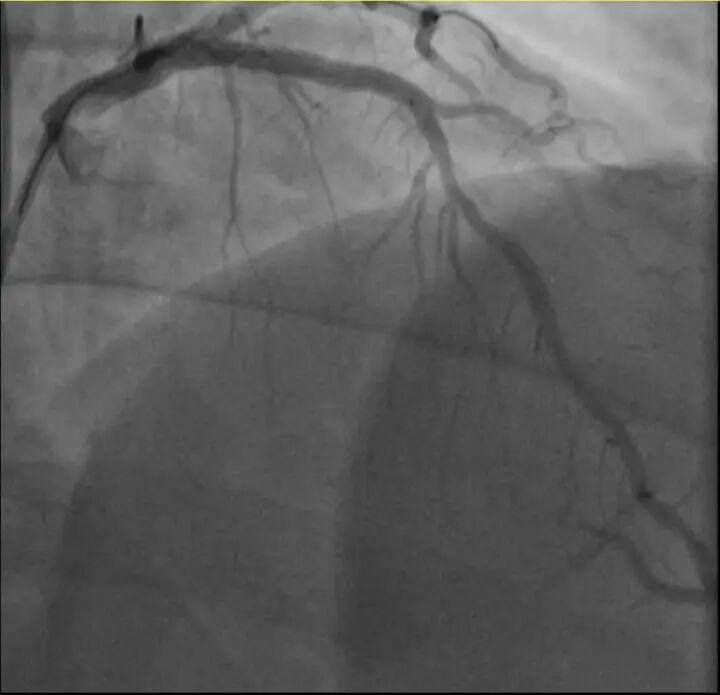

浙江医院心血管内科的医生分析,剧烈运动导致这位患者心脏的不稳定斑块破裂,进而造成前降支近段次全闭塞。所幸送医及时,孙先生的身体险情被化解。

介入治疗后影像图